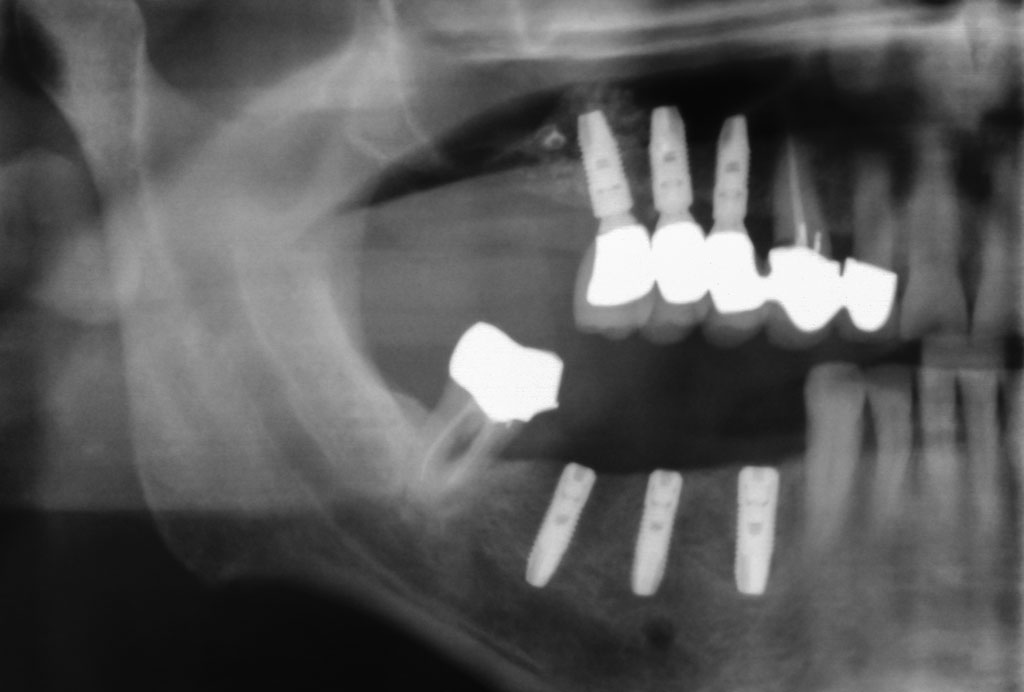

Fehlen in der Front oder im Seitenzahnbereich mehrere Zähne, ist eine Brücke oder Prothese vollkommen unnötig. Die fehlenden Zähne können entweder einzeln durch eine entsprechende Anzahl von Implantaten oder durch implantatgetragene festsitzende Brücken ersetzt werden. Das Bild der Kronen zeigt die drei Verschraubungen deutlich, im Mund liegen diese verdeckt am Gaumen oder im Bereich der Zunge.

DVT mit 3D-Planung